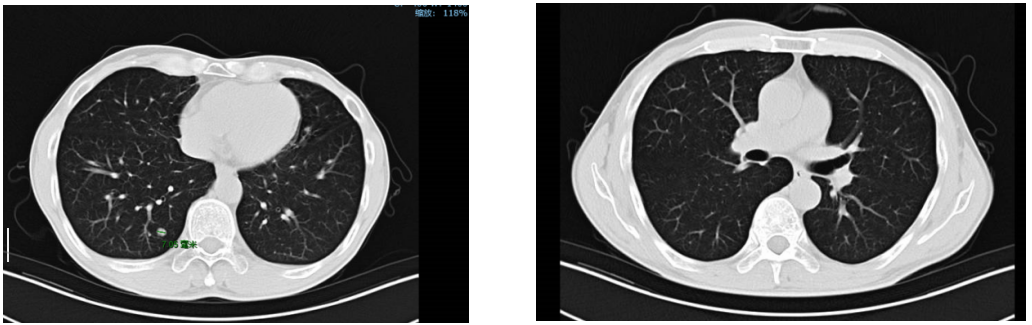

2018年8月10日复查胸部CT发现双肺多发小结节,遂定期观察随访。

2018年10月复查双肺结节较前增大。